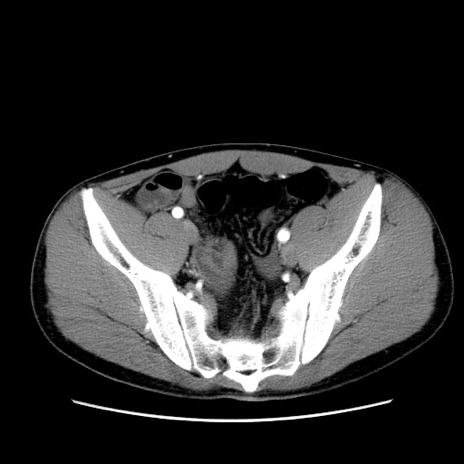

冠状断像

【症例】20歳代 男性

【主訴】心窩部痛

【現病歴】今朝より上腹部痛あり。一旦軽快していたが再度出現したため救急要請。昨日夕に白身の魚を含む刺身を食べた。

【身体所見】BP 136/89mmHg、HR 74/min、BT 37.0℃、腹部:膨満、軟、心窩部に圧痛あり。反跳痛なし、筋性防御なし、腸雑音やや亢進あり。

【データ】WBC 17700、CRP 0.48